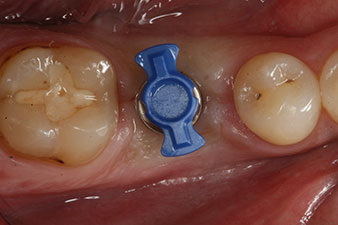

След зарастване на меките тъкани, стабилността на импланта е измерена отново преди протетичното възстановяване.

И двете стойности са практически непроменени и са между средния и високия диапазон, където по-ниската стойност винаги се използва като референтна стойност, която определя лечението.

Следователно, успешната остеоинтеграция и адекватната биологична стабилност могат да бъдат записани, което даде възможност да се вземе отпечатък в една и съща сесия.